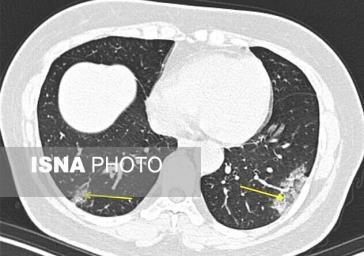

یک مطالعه جدید نشان میدهد که سی تی اسکن ممکن است در تشخیص سریعتر کروناویروس به کادر پزشکی کمک کند. پزشکان بیمارستان مونت سینای در نیویورک اولین کسانی بودند که در ایالات متحده اسکن ریه بیماران مبتلا به این بیماری بسیار مسری را تجزیه و تحلیل کردند. آنها گفتند که میتوانند الگوهای خاصی در ریهها را به عنوان نشانگر ویروس، که با نام COVID-۱۹ نیز شناخته میشود، شناسایی کنند.

محققان میگویند که این تشخیص سریعتر میتواند به آنها کمک کند تا فرایند قرنطینه کردن بیماران را زودتر و پیش از ظهور دیگر علائم این بیماری آغاز کنند. آنها با سی تی اسکن میتوانند میزان تخریب بافت ریه افراد را مشاهده کنند و این کاری است که توسط اسکنهای دیگر مانند اسکن اشعه ایکس قفسه سینه امکانپذیر نیست. بنابر گفته پزشکان ظاهرا ریه بیماران مبتلا به کرونا الگو و نشانه خاصی دارد که با بررسی سی تی اسکن میتوان این بیماری را چند روز زودتر تشخیص داد.

طی این مطالعه که در مجله Radiology منتشر شده است، پژوهشگران سی تی اسکن ۹۴ بیمار را در چهار مرکز پزشکی در چهار استان چین مورد تجزیه و تحلیل قرار دادند. بیماران بین ۱۸ ژانویه و ۲ فوریه بستری شده بودند و همه یا اخیرا به ووهان - مرکز شیوع بیماری - سفر کرده بودند یا با یک فرد آلوده در تماس بودند. رادیولوژیستها اسکن را بررسی کردند و بر اساس زمان بروز علائم و زمان انجام سی تی اسکن، یادداشتبرداری کردند. آنها دریافتند توسط سی تی اسکن میتوانند چند روز زودتر وضعیت تخریب بافت ریه را مشاهده کنند. این کار میتواند به پزشکان در تشخیص زودتر بیماران کمک بسیار بزرگی کند؛ چراکه با تشخیص زودتر عملیات قرنطینه و درمان زودتر آغاز میشود. تاکنون بیش از ۸۲ هزار نفر در سراسر جهان به این ویروس آلوده شدهاند و بیش از ۲ هزار و ۸۰۰ نفر نیز جان باختهاند.